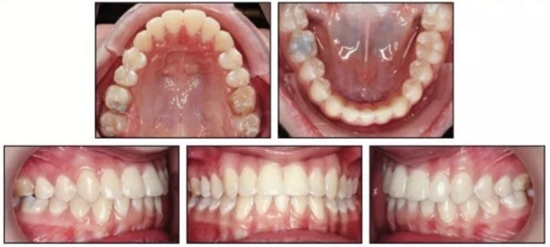

治疗结束后,患者双侧达到安氏I类关系,正常的覆合覆盖及接近理想的前牙轴倾度。头侧结果再次确认了通过上颌伸长安氏III已得到矫正,SNA从73.1°增大到78.1°(表1)。上颌前磨牙间宽度增加了约9mm。下颌MP-PP角减小了4.9°,面型接近中等面型。

患者继续佩戴活动保持器,治疗后13月随访提示其仍处于一个稳定的咬合关系。(图5)